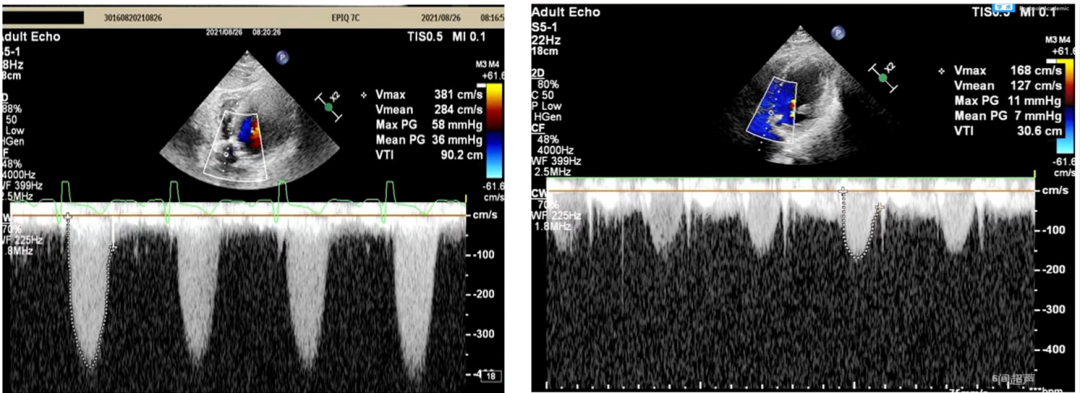

术后超声:

术后压差显著改善,无反流,患者血压良好。

植入后心衰及血流动力学都有效改善,术后Vmean1.6M/S,Pgmean 7mmHg。